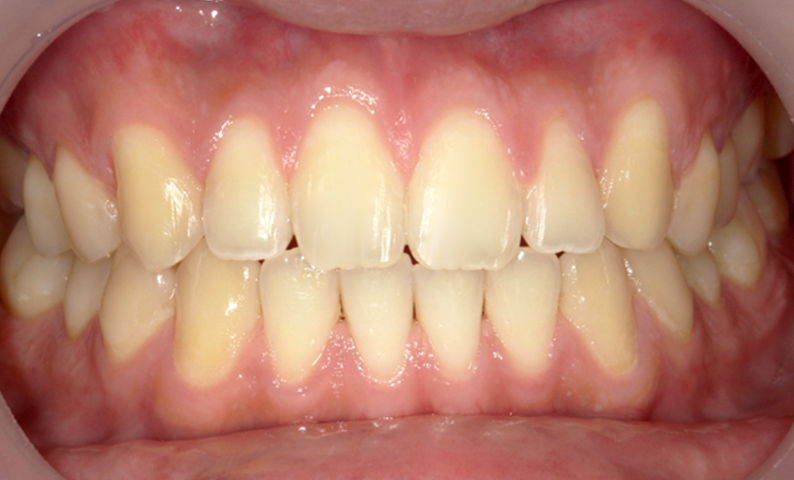

前歯の隙間「すきっ歯」と矯正治療

前歯の歯列において、隙間が生じることを一般的に「すきっ歯」といいます。

「すきっ歯(すきっぱ)」は、主に前歯に見られ、目立ちやすく、多くの人がこれを気にしています。

そのため、人前で大きな口を開けて笑うことが抵抗感を生む場合もあります。

| 治療前 | 治療後 |

|---|---|

|